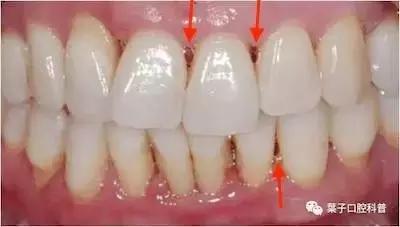

如果两颗牙齿之间的牙龈乳头畏缩(牙龈萎缩),就会造成两颗牙齿之间下方出现空隙,食物就比较容易在嘴唇、脸颊和舌头的运动作用下,水平地进入了间隙,造成了“卡肉”的现象。